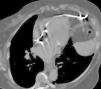

Mulher de 74 anos, com colocação de pacemaker definitivo (VDD) há cerca de 2 anos por BAV de 3.° grau, sem intercorrências, recorre à consulta de pacemaker de rotina. Não apresentava qualquer sintomatologia. Foi detetada disfunção do pacemaker (undersensing e falhas de captura), tendo-se realizado radiograma do tórax em incidência póstero-anterior que mostrou projeção extracardíaca da extremidade do eletrocateter (Figura 1). A doente foi submetida a tomografia computorizada (TC) torácica, com aquisição espiral multidetetores (TCMD 16 cortes) e reconstruções multiplanares 2D (RMP) e 3D que confirmou a localização extracardíaca da extremidade do eletrocateter, com topografia intratorácica justadiafragmática (Figuras 2–4).

TCMD com RMP em plano axial oblíquo demonstrando o trajeto do eletrocateter, parcialmente intraventricular, atravessando depois o miocárdio da parede livre do ventrículo direito e com topografia da sua extremidade na gordura paracardíaca esquerda, próximo da parede torácica. Ausência de derrame pericárdico ou de alterações valorizáveis da gordura mediastínica.